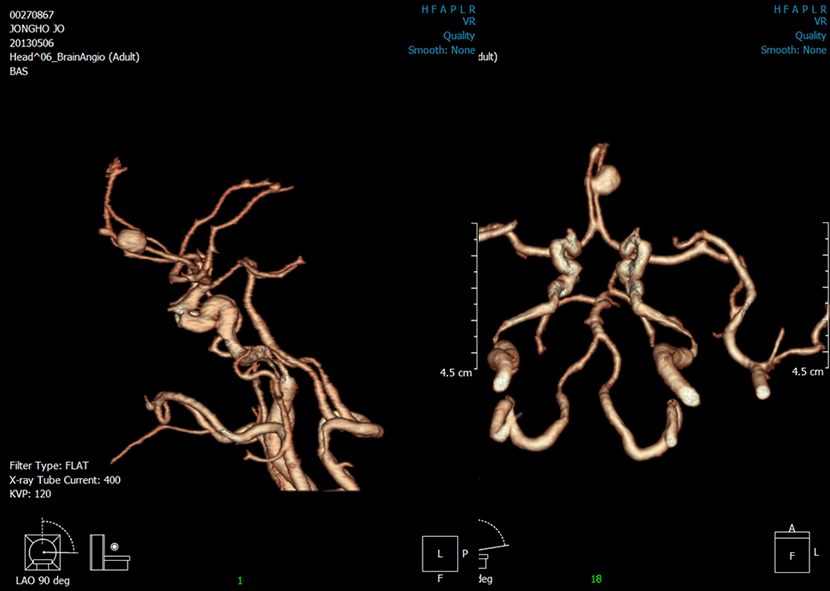

CT 혈관조영술상 뇌동맥류 발견

뇌혈관조영술로 동맥류에 대해 정밀검사